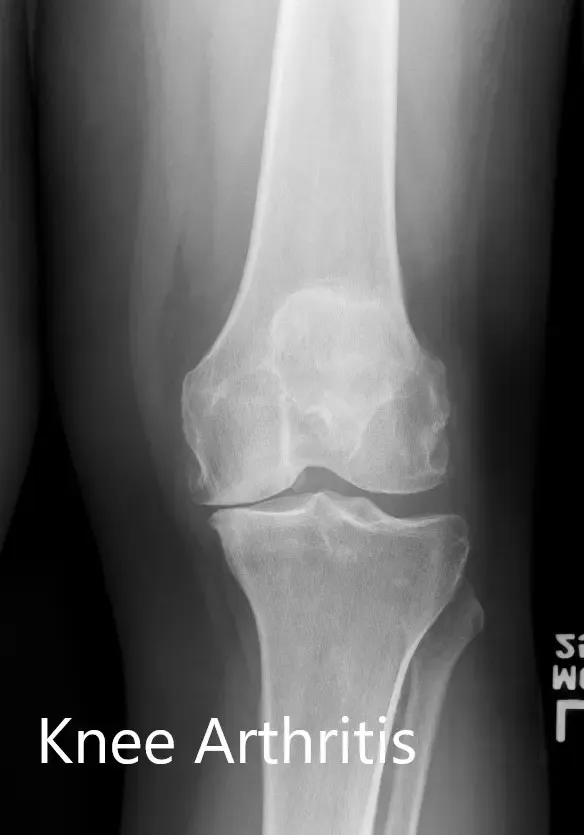

The images studies revealed tricompartmental osteoarthritis of the left knee. Considering lifestyle limiting knee pain, the patient was advised to undergo customized left knee replacement. Risks, benefits, and alternatives were discussed with the patient and her family. They all agreed to go ahead with the surgery.

Preoperative X-ray of the left knee showing AP and lateral views